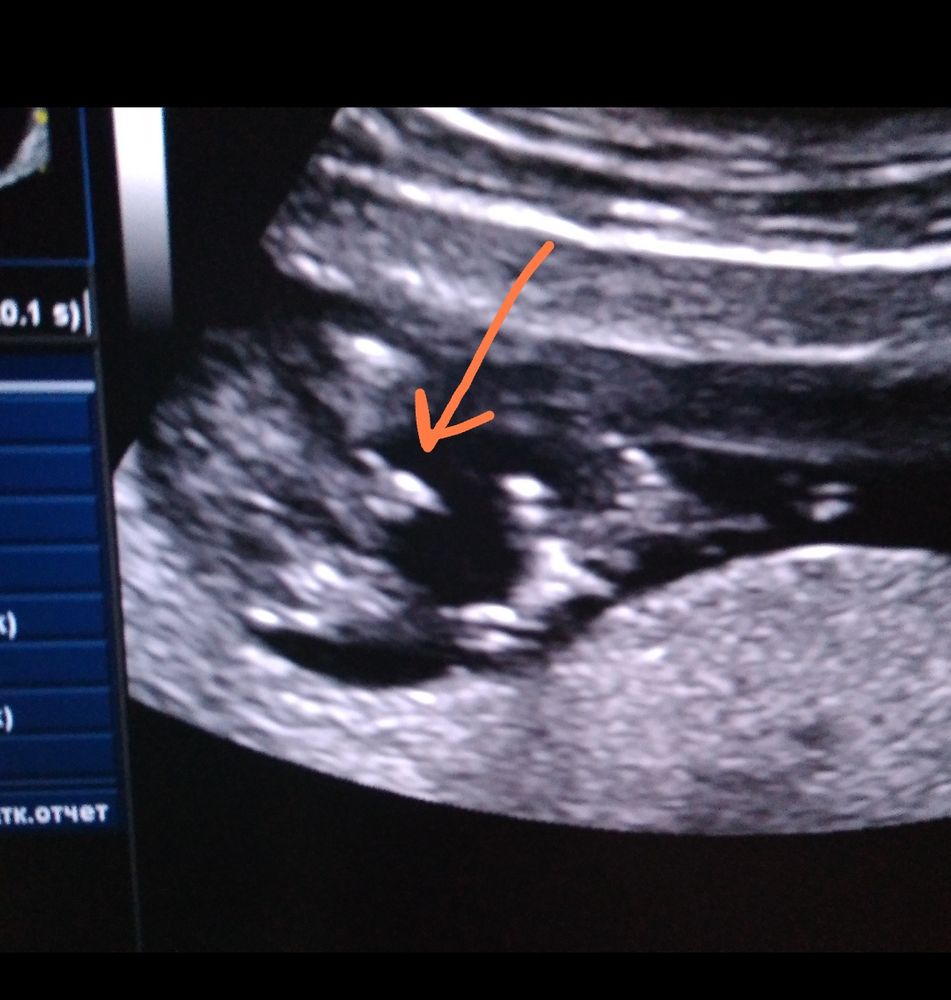

Ruzan Ruzanna в Клуб беременных 3 года Пол малыша фото узи Пол малыша Девочки кто разбирается девочка или мальчик Посмотрите еще 20 записей на эту тему Лучший ответ Катя Мальчик 20.05.2023 Ответить Отменить Ответить Екатерина Похоже на девочку. У сын вот так было по узи 20.05.2023 Ответить Пол малыша 12 недель Ошибки во время узи! Чаты Беременных Выберите чат: Январята-2026 Февралята-2026 Мартята-2026 Апрелята-2026 Майчата-2026 Июнята-2026 Июлята-2026 Августята-2026